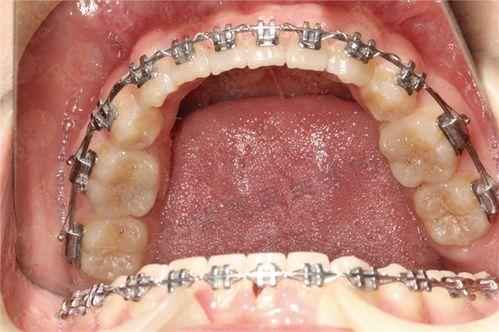

牙齒矯正可能出現(xiàn)的副作用

二、牙齒矯正可能出現(xiàn)的副作用